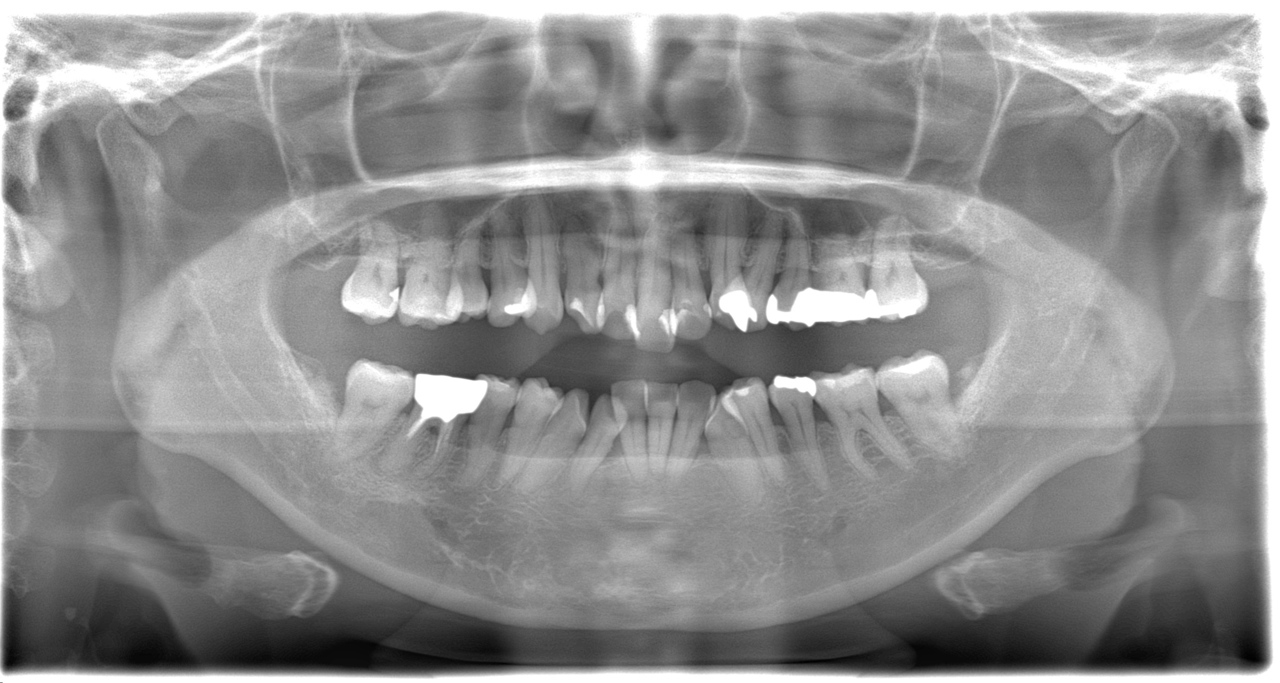

歯ならびの治療を主訴にご来院されました。上顎前歯の突出がみられ、唇が閉じにくく、麺類が食べにくいとのことでした。まず、保険診療で歯周病の治療を行いました。ワイヤー矯正とインビザラインによる矯正治療を説明し、ワイヤー矯正治療を希望されました。まず、歯を並べるためのスペースを確保するため、上顎小臼歯の抜歯を行いました。その後は、レベリング、リトラクション、正中合わせ、コントラクション、アイデアルアーチによる最終調整をしました(専門用語ですみません)術後は、食べ物が食べやすくなったこと、見た目が改善されたことを喜ばれていました。全体的に歯周病の進行が見られるため、今後は歯周病安定期治療による定期的な治療を続けていきます

歯根の吸収など